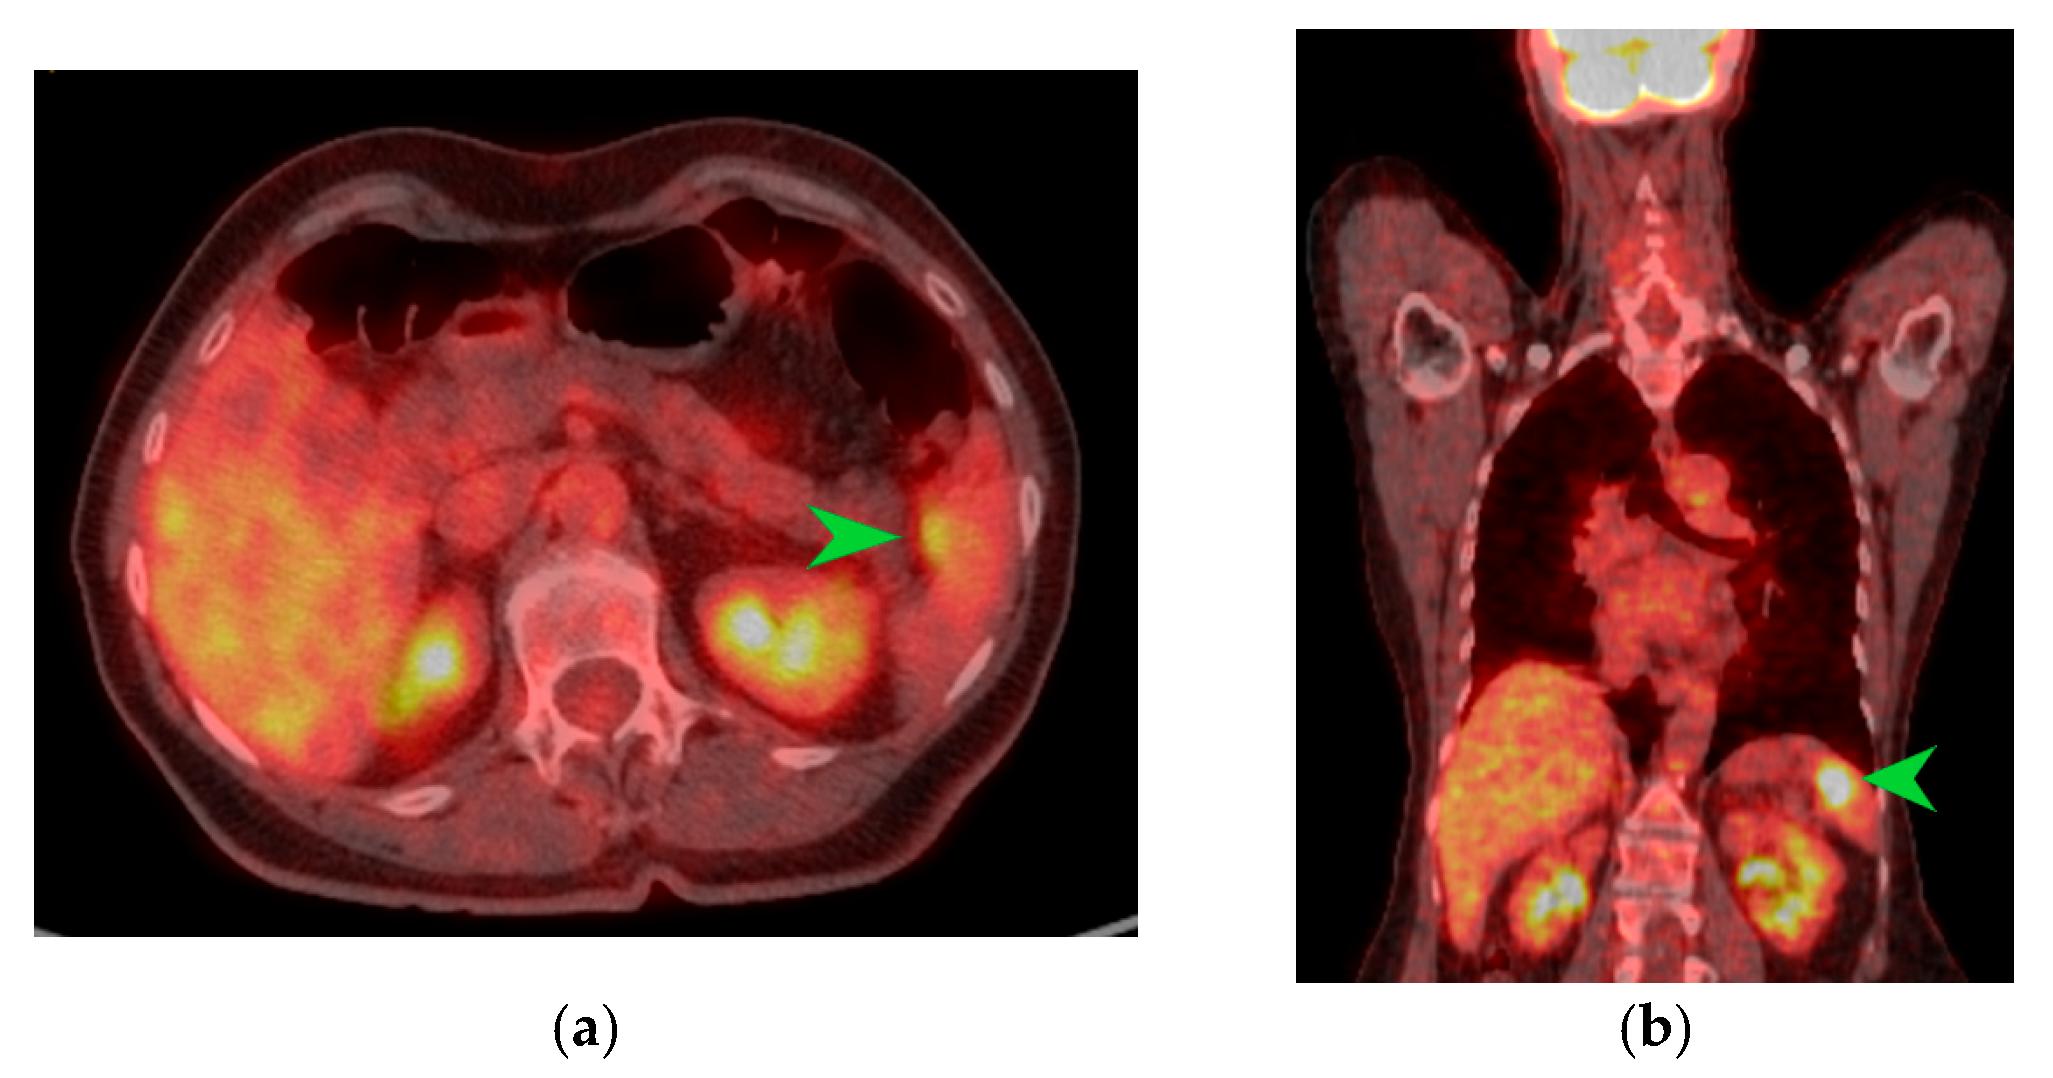

Figure 3.

PET-CT images in transverse (a) and coronal (b) sections highlighting an area of metabolic activity in the spleen that raises suspicion of splenic metastasis. The splenic tumor is indicated by the green arrow.

The macroscopic examination of the gastric resection specimen revealed a tumor ulceration of 3/2.5 cm (Figure 1a). Microscopic evaluation confirmed the presence of moderately differentiated intestinal-type gastric adenocarcinoma (G2), infiltrative in the subserosa, with vascular tumor emboli present (Figure 1b). Twenty-eight lymph nodes were identified, and tumor invasion was confirmed in five of them. The surgical resection margins were free of tumor invasion. Postoperatively, the patient remained under oncological follow-up, and approximately 10 months postoperatively, he reported significant weight loss and physical asthenia, symptoms that were initially considered to be associated with the complex treatment of the neoplastic disease. However, serum determination showed a slight increase in CEA to 6.5 ng/mL from 3.2 ng/mL and an increase in CA19-9 to 160 U/mL from 21 U/mL (Table 1), which led to the decision to perform an abdominal CT that revealed the presence of a hypodense, poorly iodophilic splenic lesion, measuring 23.5/16 mm, raising suspicion of a splenic metachronous metastasis (Figure 2). The imaging examination was continued with a PET-CT scan, which highlighted the pathological uptake of 18F-2-deoxy-2-fluoro-glucose (18F-FDG) at the level of the previously described lesions without detecting other areas of suspected metabolic hyperactivity (Figure 3).

On the other hand, a contrast-enhanced CT examination in patients with suspected splenic metastases provides important diagnostic information; however, performing a PET-CT with 18F-FDG highlights the increased metabolism at the level of the splenic tumor and increases the chances of diagnosis. According to studies, the 18F-FDG PET-CT examination seems to have the highest negative predictive value for malignancy in the case of splenic tumors discovered through other imaging investigations [21]. Confirmation of the diagnosis through ultrasound-guided fine needle biopsy of the spleen is feasible, showing a sensitivity of 98.4% and a positive predictive value of 99.2%, with major post-procedure complications being under 1% [22,23].